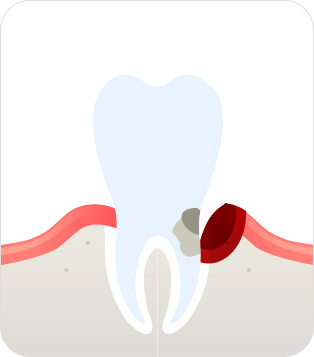

치주염(말기)

치조골 손실이 심해져

치아가 흔들리다 결국 빠지게 됨